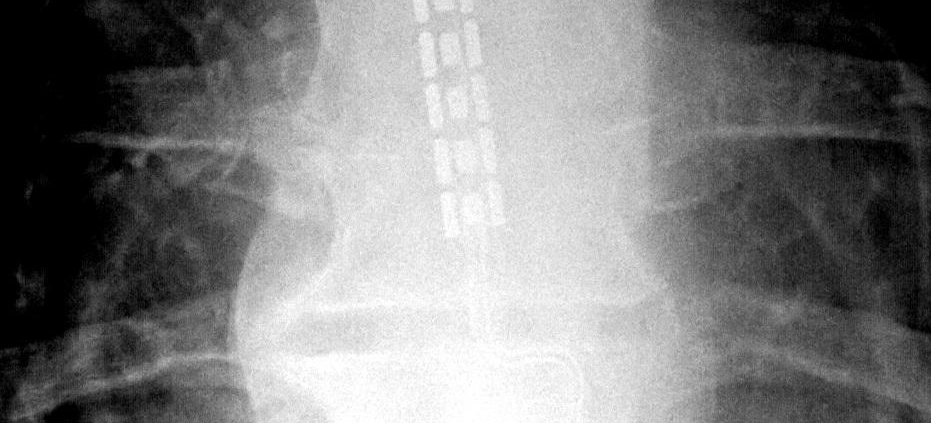

The Spinal Cord Stimulator (SCS) is a device used to exert pulsed electrical signals to the spinal cord to control chronic pain. SCS systems consist of an implantable pulse generator, a lead, and a remote control. The device is implanted via a minor surgical process and can help patients manage longstanding pain that hasn’t responded well to other treatments.

Spinal Cord Stimulation is typically recommended when other treatments have not worked. The procedure consists of implanting a spinal cord stimulator device under your skin. The device delivers a low-level electrical impulse to your spinal cord or specific nerves to block pain.